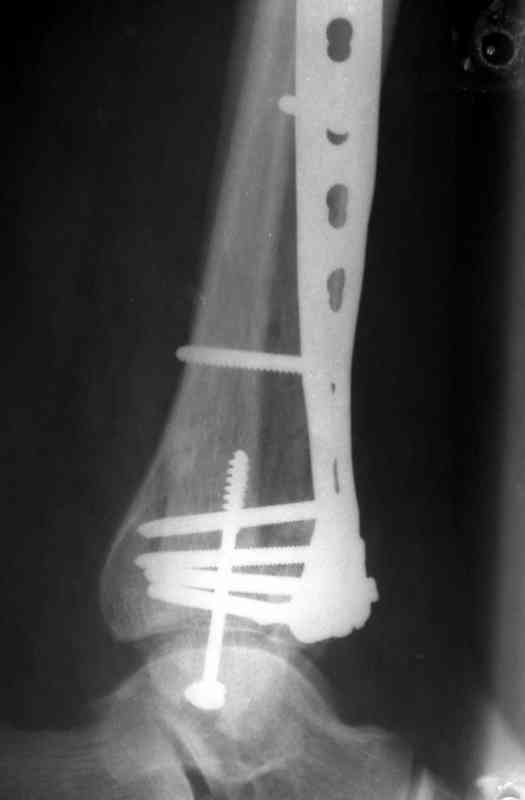

Re: Perelom N/3 kostei goleny

Дрягин В. 04 Январь 2007, 13:23

Посылаю результат лечения предыдущего больного через год.

С уважением Дрягин